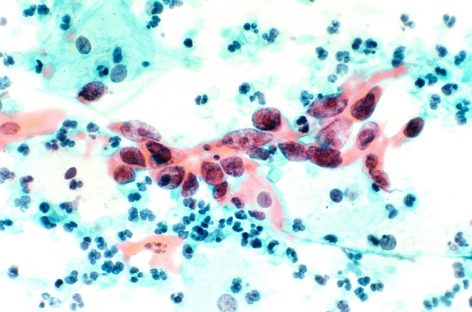

STUDIU: Persoanele cu cancer de sân inflamator prezintă un risc mai mare de metastaze la creier 21 oct 2022